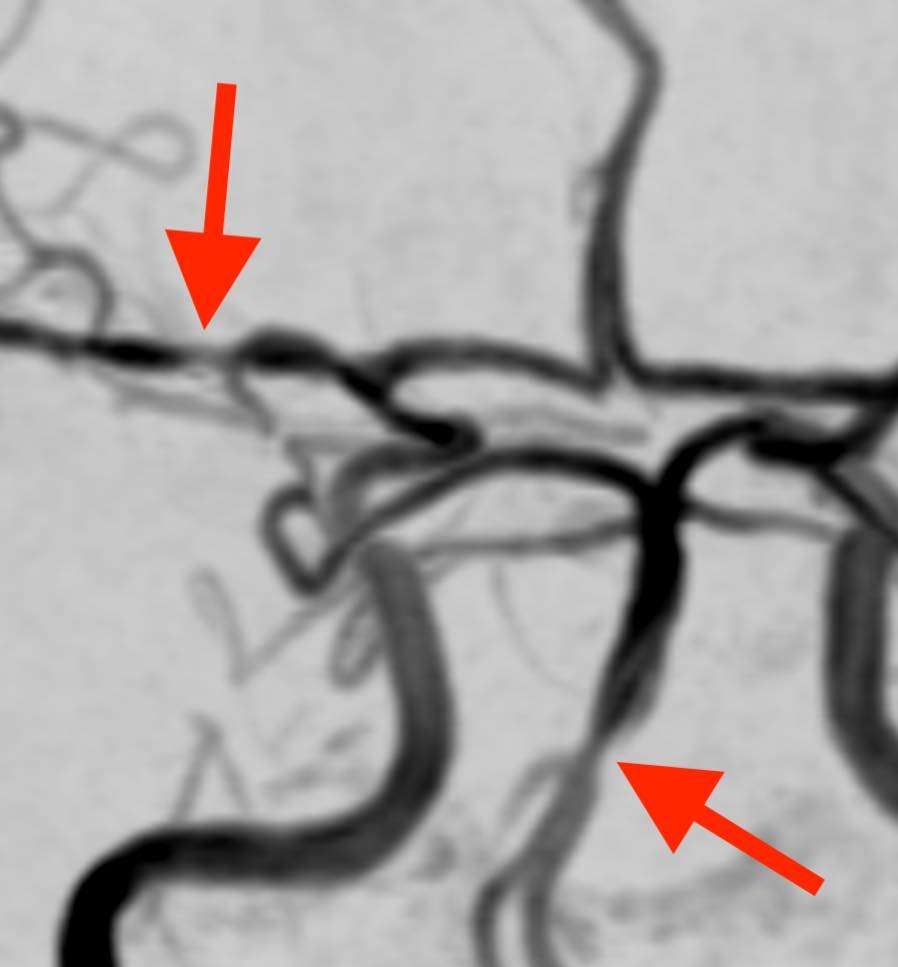

頭部MRA検査で脳の血管を撮影しました。

脳底動脈や中大脳動脈など比較的太い血管に、くびれて細くなった部分とソーセージのような形の部分とが見られています。脳自体には異常はありませんでした。

症状の経過と画像所見から、可逆性脳血管攣縮症候群(RCVS)と診断しました。可逆性脳血管攣縮症候群(RCVS)は、咳やくしゃみ、鼻をかむなどの動作で誘発される事があります。1) 2)